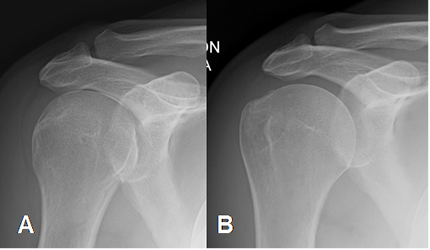

Fig 5. Proyecciones del hombro.

A: Rx en rotación interna y B: Rx en rotación externa.